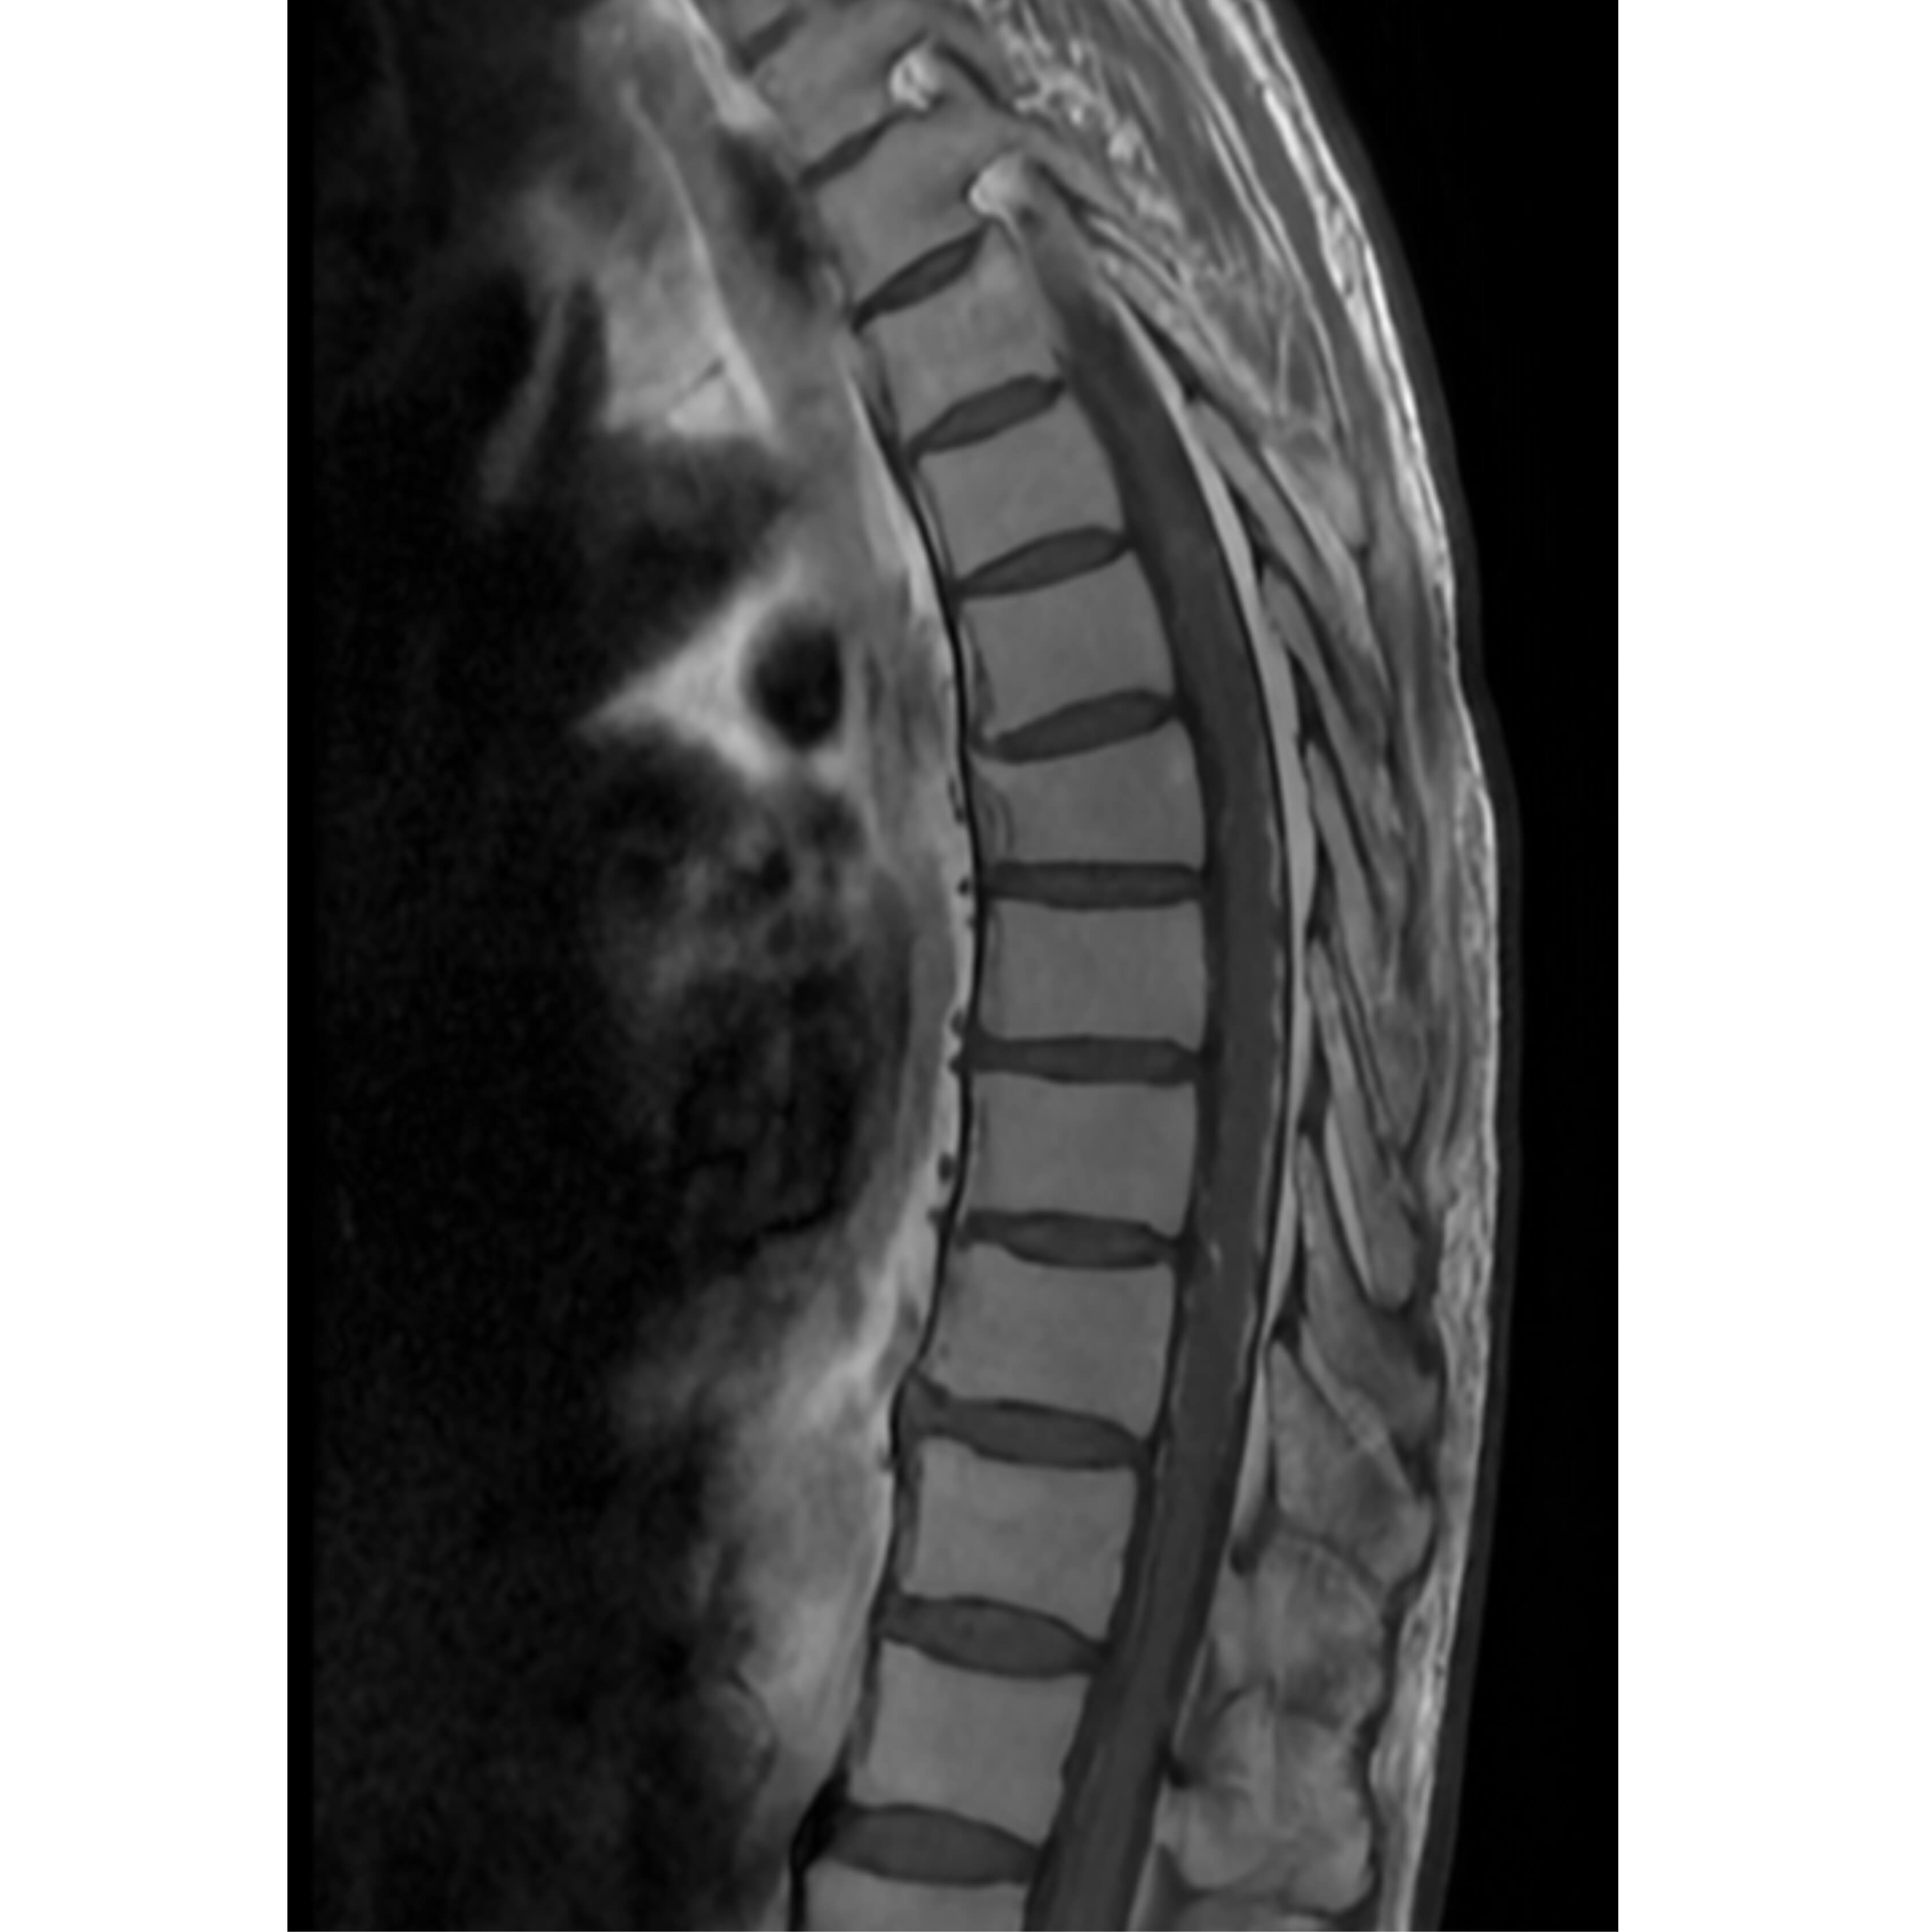

تمكّن الفريق الطبي في وحدة القسطرة بالمستشفى التخصصي، بقيادة الدكتور حازم حبوب استشاري الاشعة التداخلية، من إجراء تداخل طبي متقدم لمعالجة حالة شلل طرفي ناتج عن وجود تشوه شرياني وريدي في النخاع الشوكي، وذلك تحت المراقبة الفسيولوجية العصبية الدقيقة.

وتمت العملية بنجاح من خلال استحضار الإمكانيات الحسية والحركية للمريض أثناء الإجراء، لتفادي أي مضاعفات محتملة. وأسفرت العملية عن تحسن ملحوظ في حالة المريض، حيث أصبح قادراً على المشي بشكل أفضل وبمفرده، إضافة إلى استعادته السيطرة الكاملة على وظائف الجهاز الهضمي.